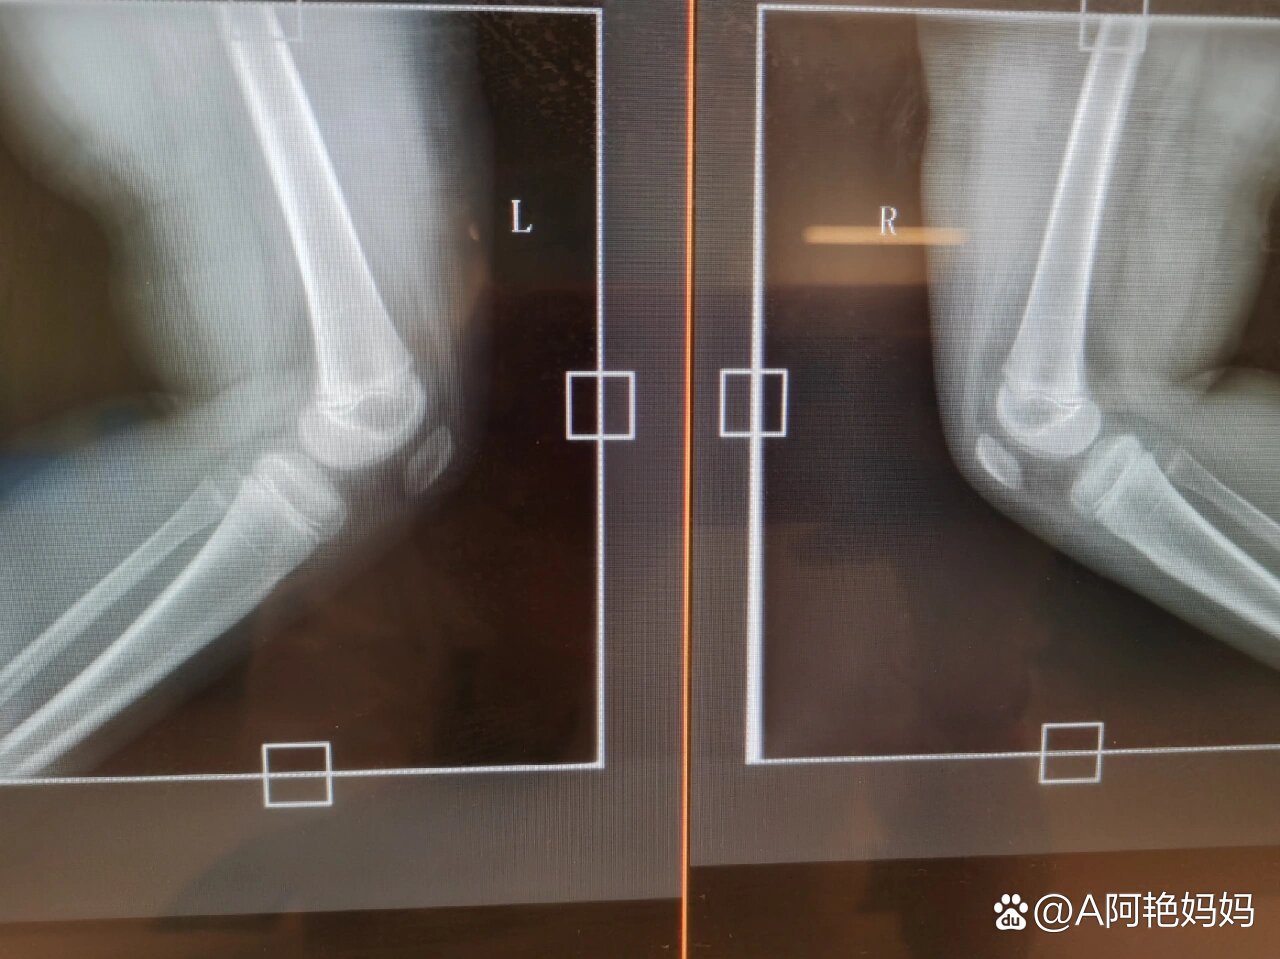

2岁儿童膝关节髌骨骨化情况

图片尺寸4608x2128